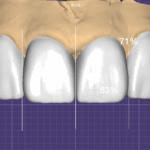

사진 2, 3. 라미네이트 제작 과정

이 케이스에서도

치아 전체를 두껍게 덮는 방식이 아니라,

- 치아 사이 공간을 중심으로

- 앞면을 최소 범위로 감싸는 디자인

을 적용했습니다.

이는

사진 4. Try-in 모습

실제 치아 위에 올려보면

라미네이트의 얇기와 투명도가 그대로 드러납니다.

무삭제 라미네이트의 경우

자연치아 색이 그대로 비쳐 보이기 때문에

세라믹의 선택과 제작 방식이 결과를 좌우합니다.